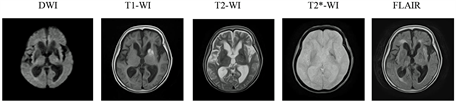

Patient 1 is an 87-year-old woman, referred to our hospital owing to right side hemiballism. She had taken 1 mg glimepiride (sulphonylurea) and 50 mg sitagliptin (Dipeptidyl peptodase-4 inhibitor; DPP-4I) for diabetes. Laboratory data on admission showed glycated hemoglobin (HbA1c) at 8.4%, plasma glucose at 68 mg/dL, and an estimated glomerular filtration rate (eGFR) of 31 ml/min/1.73 m2 suggesting chronic kidney disease. Head MRI T1-WI revealed a high intensity area in the left side of putamen and caudate nucleus, but nothing remarkable was found in diffusion weighted images (DWI) or T2-WI (Figure 1(a)). She was diagnosed as having DC due to oral hypoglycemic agents. After discontinuing glimepiride, hypoglycemia was not observed. DPP-4I leads to renal impairment; subsequently, the treatment course was changed to 5 mg Trazenta®. Following the treatment change, the daily glucose levels were 110 - 200 mg/dL and choreic movement improved. For further rehabilitation, she was transferred to another hospital on eighth day in our hospital. Patient 2 is a 51-year-old woman with uncontrolled hyperglycemia, hospitalized owing to loss of conscious. Laboratory

Figure 1. (a) Magnetic resonance imaging (MRI) findings of patient 1 showed a high intensity area in putamen and caudate nucleus in T1-weighted image (T1-WI); (b) Multiple small hyperintensities in both periventricular sides in diffusion weighted image (DWI) and fluid-attenuated inversion recovery (FLAIR), with normal looking putamen and caudate nucleus in T1-WI of patient 2. DWI; diffusion weighted image, T1-WI; T1-weighted image, T2-WI; T2-weighted image, T2*-WI; T2*-weighted image, FLAIR; fluid-attenuated inversion recovery.

data showed plasma glucose at 1290 mg/dL and pH at 7.34, but no ketonuria. After hospitalization, she started presenting right side hemiballism. We started her on an insulin and saline intravenous infusion. After 6 days, we performed a head MRI and found multiple small hyperintensities in both periventricular sides by DWI and fluid-attenuated inversion recovery (FLAIR) (Figure 1(b)). T1-WI showed no lesions in putamen and caudate nucleus. There was no evidence of carotid plaques, atherosclerosis of brain arteries, or arrhythmia. We diagnosed her as having DC with hyperosmolar hyperglycemic state. We controlled hyper glycemia using insulin injections. We administered haloperidol at 0.75 mg/day and gradually increased up to 2.25 mg/day. After glycemic control and haloperidol administration, the choreic movement improved and the patient was able to self-administer insulin injection (final dose of insulin; insulin glargine U300 19 U, insulin glulisine 2-2-2 U). She was transferred to another hospital for further rehabilitation on twenty-ninth hospital day.

Patient 1 showed the typical MRI findings of DC. Because SU and DPP-4I combinations are known to cause hypoglycemia [7] , and the patient presented no hyperglycemia on admission, we considered that the use of SU and DPP-4I may have led to hypoglycemia and subsequent DC. There is also been a report of an elderly woman with type 2 diabetes and hypoglycemia associated with insulin treatment that led to DC [6] . It is possible that the hypoglycemia also associated with diabetes therapy in elderly patients may cause DC. A case series of 53 patients with DC revealed that all patients showed a high intensity in basal ganglia on the MRI T1-WI [4] . Hyper intensity in basal ganglia is a typical MRI finding and supports the clinical diagnosis of chorea in patients with diabetes. On the other hand, some cases showed no abnormalities in the basal ganglia using brain MRI [5] [8] . One case showed leukoaraiosis and multiple cortical ischemia, but no hyperintensisty in putamen [9] . A recent study reported that a DC patient with nonketoic hyperglycemia did not show any abnormalities in the brain MRI and computed tomography (CT) [10] . In our case, patient 2 did not show typical DC symptoms, such as high intensity area in basal ganglia in the brain MRI. Instead, we found multiple small hyperintensities in both periventricular sides in the DWI, but the typical putamen high intensity on the T1-WI was not found. Hyperviscosity caused by extreme hyperglycemia may produce a transient microcirculatory dysfunction of the striatum [11] . Recently, some patients had been reported to present chorea due to essential thrombocythemia or polycythemia vera [12] [13] . We think it is possible that hyperviscosity due to extreme hyperglycemia led to multiple cerebral thromboembolisms in our patient 2. In addition, the lack of evidence for atherosclerotic lesions in the carotid artery ultrasonography and the brain magnetic resonance angiography added to a lack of arrhythmias support the notion that these multiple small hyperintensities did not represent atherosclerotic lesions in our patient 2. Chang et al. proposed two types of DC: a common type showing hyperglycemia, choreic movement with typical radiographic imaging in brain MRI or CT and uncommon type showing chorea with negative imaging changes [10] . Patient 2 exhibited uncommon type of DC. However, there is no clear evidence about the uncommon DC. It is, therefore, necessary to report such patients.